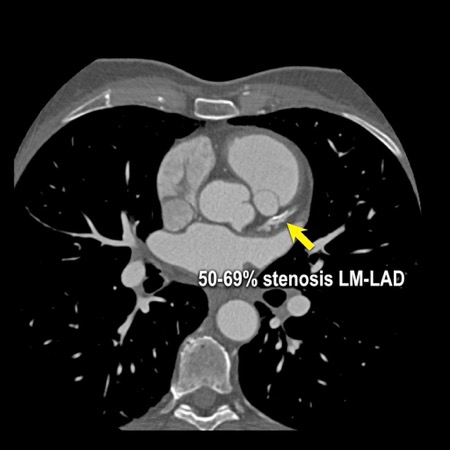

The findings are:

artefacts. - Calcified plaque in

the D1 causing severe stenosis (70-99%) at the origin (white arrows). - Partially calcified

Due to severe stenosis in D1, extensive plaque burden, some

non-diagnostic segments and a stent this patient classifies as CAD-RADS

4A/P4/N/S, which means that this patient needs further workup.